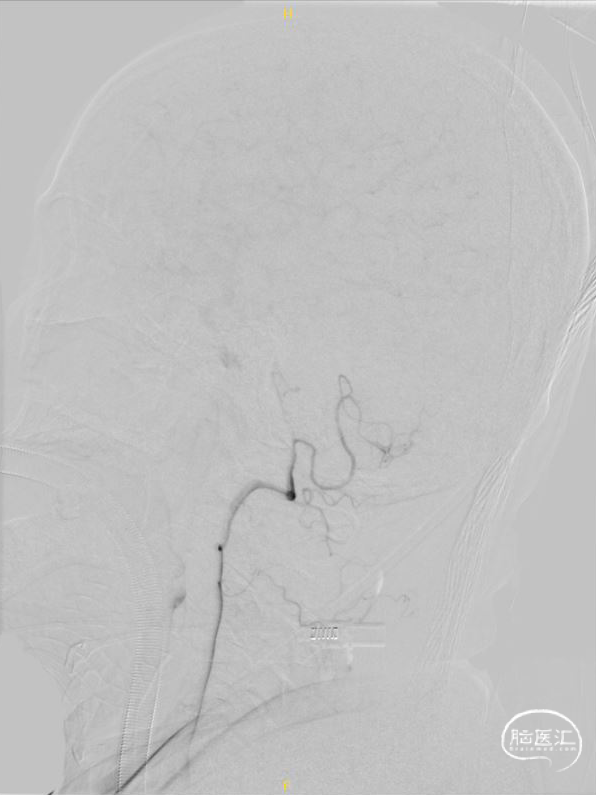

右椎正侧位造影提示:右椎止于小脑下后动脉。

左椎正侧位造影提示:血流缓慢,左椎起始部迂曲,BA下段重度狭窄。

超选左椎行3D旋转造影。

将8F 导引导管置于左侧锁骨下动脉,6F 115cm Navien中间导管置于左侧椎动脉V2段,调整工作角度,于路图下使用HYBRID 1214DA微导丝将SL-10微导管通过基底动脉狭窄段,并置于左侧大脑后动脉。

交换300cm Transend微导丝后,交换1.5*15mm Gateway球囊缓慢扩张。

交换3.0*15mm Wingspan支架,定位准确后释放,交换2.0*9mm Gateway球囊于支架内后扩张。

术后3D旋转造影。